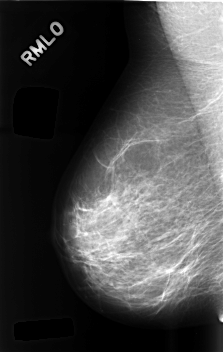

C_0489_1.RIGHT_MLO

RIGHT_MLO LINES 4576 PIXELS_PER_LINE 2912 BITS_PER_PIXEL 12 RESOLUTION 50 NON_OVERLAY